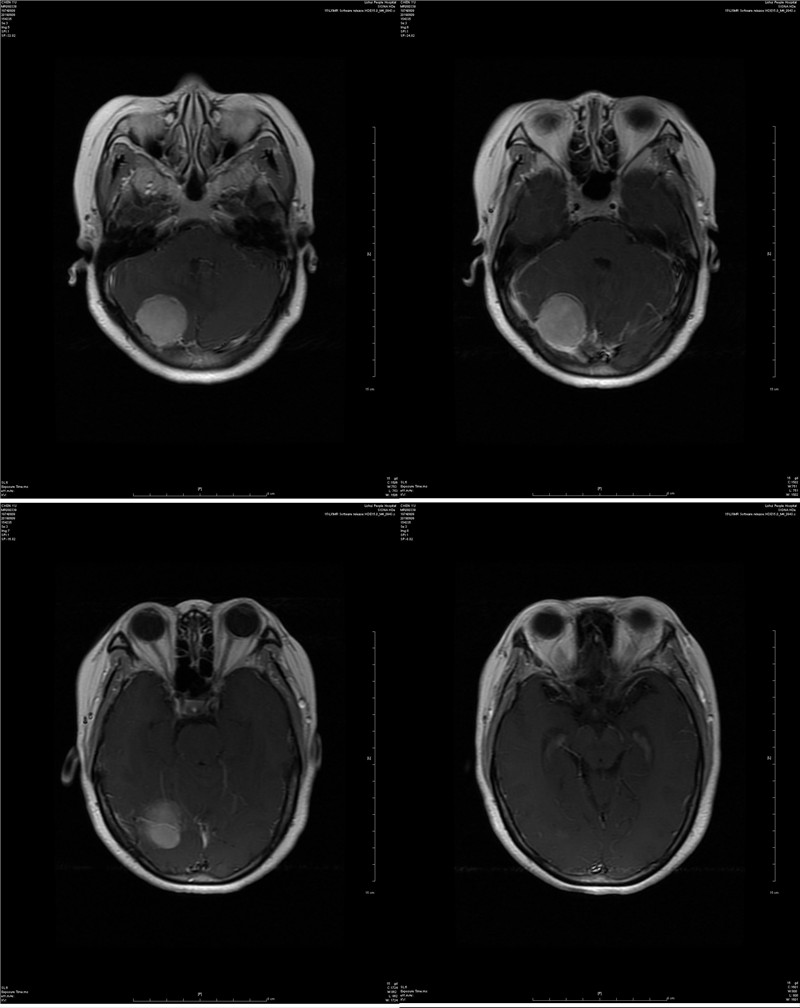

近日,神经外科收治了一例后颅窝跨天幕脑膜瘤的患者,经手术治疗后患者痊愈出院。这是我院独立完成的首例后颅窝脑膜瘤切除术,术后患者恢复良好,无手术并发症,这标志着神经外科在颅内肿瘤显微手术技术上又迈上一个新的台阶。 后颅窝是颅腔的一个特殊部位,有众多重要血管和神经穿行其中。此外,与幕上颅腔相比,后颅窝空间狭小,却容纳有脑干、小脑半球及除Ⅰ、Ⅱ神经外的所有颅神经,常因手术显露牵拉脑组织、术后脑水肿,造成严重后果,长期以来一直是神经外科手术的难题之一。 该患者一年多来偶有头疼头晕症状,经体检后发现颅内有一蛋黄大小肿瘤。患者家庭经济条件一般,子女尚未成家,面对一笔不小的手术费用深表担忧。床位医生周立田副主任医师对患者及家属耐心讲解,表示尽可能的控制住院诊疗费用,患者及家属终于打消了顾虑并决定在我院手术治疗。 经过缜密讨论研究,术前精心设计了手术方案,由神经外科杨平来主任医师、周立田副主任医师联手主刀,经过近6个小时不懈的努力和精细的操作,显微镜下成功全切肿瘤,并完整地保留了肿瘤压迫的重要引流静脉,手术取得圆满成功。 此例手术的成功开展,得益于神经外科团队技术的不断提升,神经外科将以此为动力,以精湛的医疗技术、最低的治疗费用和优质的医疗服务为溧水百姓的健康保驾护航!